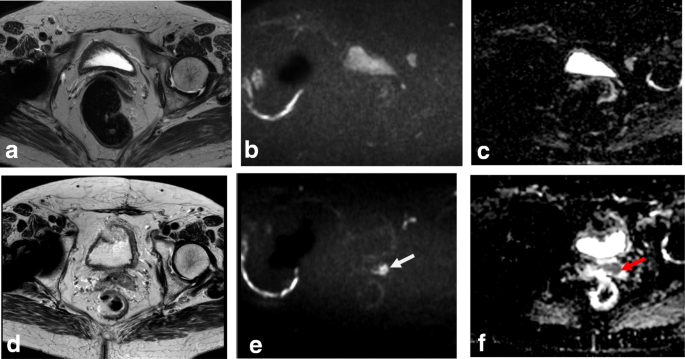

In young patients, hormonal changes during the menstrual cycle may result in a higher SI of the cervix on T2WI, similar to that of the myometrium. DWI and DCE improve the delineation and tumor-to-cervical stromal contrast of small isointense tumors that are difficult to see on T2WI (Fig. 12) [10, 11, 34, 35].

Tumor visualization with axial oblique T2WI (a), DWI-ADC map (b), and DCE imaging (c) reveals loss of the hypointense cervical rim on the right lateral aspect of the cervix, with an irregular interface between the tumor and the parametrium (arrow). ADC map shows diffusion restriction, and DCE imaging reveals enhancement of the right lateral wall indicating early parametrial invasion (arrows)